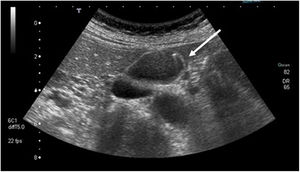

| Adenoma | Capacidad de degeneración malignaPuede ser sésil o pedunculadoHistologÃa más frecuente: tubular, papilar o tubulopapilar | Ecográficamente homogéneos, con ecogenicidad similar al hÃgado (fig. 3) |